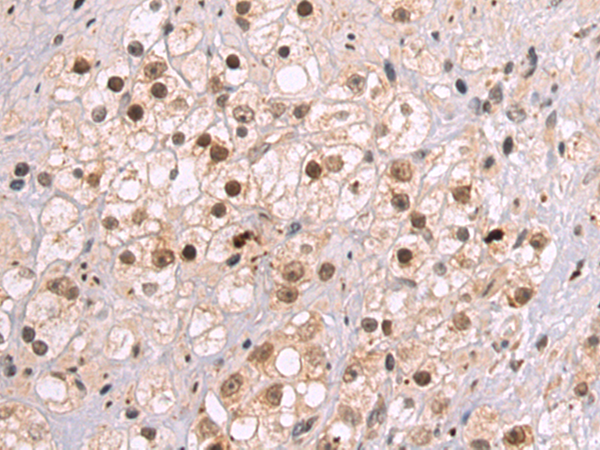

This gene encodes a member of a family of proteins containing a ribonucleoprotein (RNP)-type RNA binding motif and a carboxyl-terminal arginine-serine-rich (RS) domain. The encoded protein functions as a pre-mRNA splicing factor. There is a pseudogene for this gene on chromosome 7. Alternative splicing results in multiple transcript variants. |

SRSF8 |

serine/arginine-rich splicing factor 8 |

DSM-1; SRP46; SFRS2B |